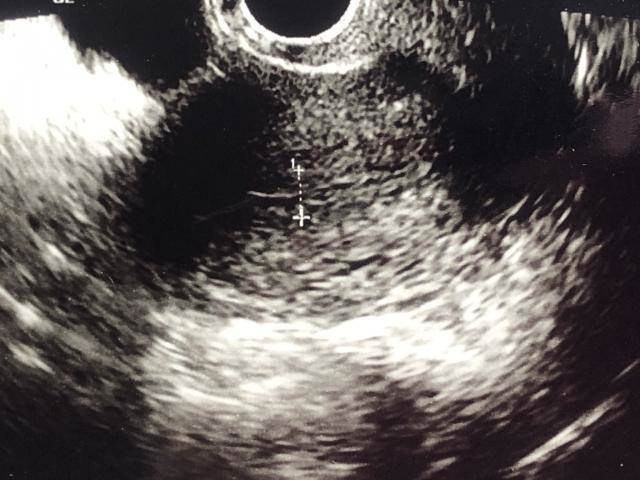

現代人的飲食習慣高油、高鹽、高糖,再加上缺少運動,可能就會導致脂肪肝。急診醫師魏智偉分享,一名高中生下課後時常以「雞排配珍奶」當正餐,某次因嚴重腹痛被送來急診,經檢查後發現竟有脂肪肝,整塊肝臟都變得「白白亮亮」,讓他相當震驚。

醫師魏智偉在節目《健康零距離》指出,曾有一名高中生病患,體型肥胖,因肚子劇烈疼痛被送到急診,檢查後確診急性胃炎。

後續進一步了解,發現該名學生下課後補習時,都會以雞排配珍奶當正餐,進而導致脂肪肝問題。魏智偉表示,只要尚未演變成嚴重的發炎影響到肝臟,脂肪肝是可逆的,只要戒掉油膩的食物,便可以恢復。